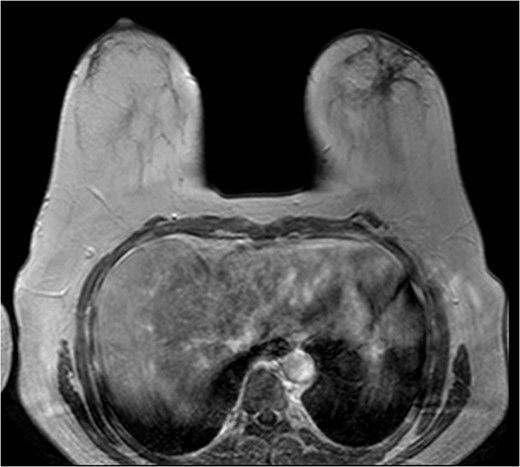

The patient was then sent for MRI of the breast to detail the extent of the remaining mass. This revealed an ill-defined mixed linear and fine nodular enhancing tumor 6.5 × 4.6 × 4.8 cm in size with BI-RADS 5 (Figs 4–7).

Due to the location of the residual lesion posterior to the nipple and its large size, simple mastectomy with sentinel lymph node biopsy was performed with immediate breast reconstruction. Breast conservation surgery was not considered secondary to the location and size. Histology showed a focus of ductal carcinoma in-situ (DCIS) with micropapillary growth and a secondary synchronous invasive ductal carcinoma 0.7 × 0.4 × 0.3 cm adjacent to the lesion. Four lymph nodes were excised and all negative for invasive characteristics. Staging indicates a T1N0M0, Stage I lesion.

The role of MRI in identifying the extent of breast carcinoma is widely reviewed. EPC has been noted to have multifocal hyperintensities at T1 weighted imaging. Contrast MRI will reveal enhancement of the cystic wall, septa and mural nodules [4].